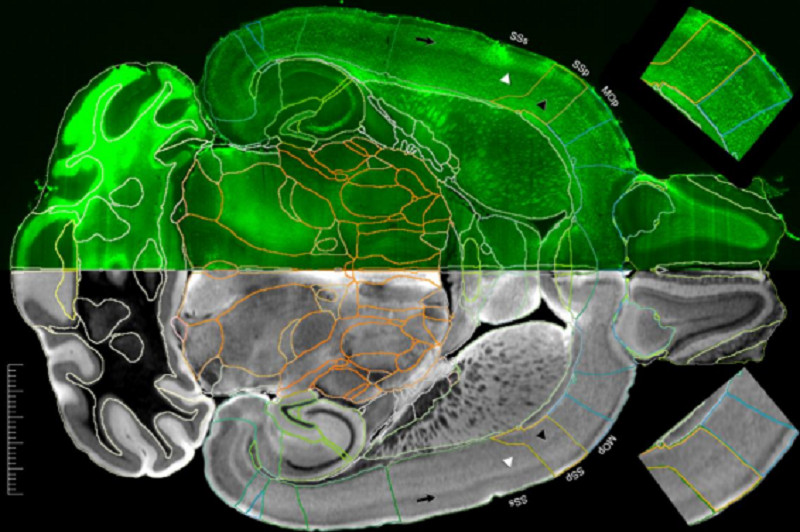

Американские ученые заявили, что смогли получить самые подробные изображения МРТ мозга мыши за всю историю исследований. По их словам, разрешение этих изображений в 27 тысяч раз превышает качество предыдущих.

С годами мощности аппаратов увеличивались, но их все еще было недостаточно для того, чтобы разглядеть самые крохотные детали строения органа и выявить патологические новообразования. Но теперь, благодаря высокому угловому разрешению, исследователи получили самые подробные из когда-либо созданных карт МРТ-соединений. И сейчас это гиперреалистичные изображения мозга.

«Изображения тензора диффузии с пространственным разрешением 15 мкм в тысячу раз превышают разрешение большинства доклинических МРТ грызунов. А изображения плотности дорожек со сверхвысоким разрешением в 27 тысяч раз превышают типичные доклинические изображения МРТ», — рассказал Дж. Аллан Джонсон, профессор радиологии Университета Чарльза Путмана, директор Центра микроскопии in vivo при Университете Дьюка.